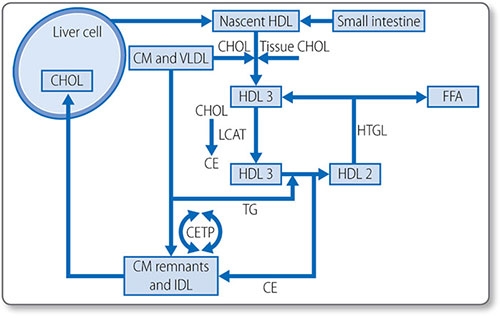

Figure 1.46: Biosynthesis of cholesterol. HMG-CoA, 3-hydroxy-3-methylglutaryl CoA. NADPH, nicotinamide adenine dinucleotide phosphate; ATP, adenosine triphosphate.

This process starts with the isomerization of isopentenyl pyrophosphate to form dimethylallyl pyrophosphate.

Formation of squalene epoxide The third stage is the cyclization of squalene to form squalene epoxide. This requires O2 and NADPH. Squalene epoxide then undergoes cyclization to lanosterol in a reaction catalyzed by cyclase. Lanosterol is then converted to cholesterol, a 27-carbon molecule, by the removal of three methyl groups and the reduction of a double bond by NADPH.

79Regulation of cholesterol synthesis Cholesterol synthesis is regulated by mechanisms that sense the cellular level of cholesterol and modify HMG CoA reductase levels and activity:

- Sterol regulatory element: a transcription factor that inhibits enzyme gene expression in the presence of sterols

- Non-sterol metabolites: derivatives of mevalonate inhibit enzyme gene expression

- AMP-activated protein kinase: phosphorylates and decreases enzyme activity when ATP levels are low

- Enzyme degradation is also tightly regulated.

Cholesterol absorption

Cholesterol esters in the gut are hydrolyzed by cholesterol esterases, secreted by the pancreas and small intestine, to free cholesterol. Cholesterol must be emulsified to be absorbed: conjugated bile acids form micelles with free cholesterol, fatty acids, monoglycerides, and phospholipids.

Most cholesterol is absorbed in the middle jejunum and terminal ileum through the transmembrane transporter protein Niemann–Pick C1-like 1 protein. 30–60% of dietary cholesterol is absorbed daily. Once absorbed into the intestinal mucosa cell, it is packaged into large lipoproteins called chylomicrons.

Cholesterol esterification

As free cholesterol is cytotoxic, it is esterified in the liver to cholesterol ester by acyl cholesterol acyl transferase. Cholesterol esters are stored in intracellular lipid drops and constitute 70% of plasma cholesterol.

Esterification requires energy-dependent activation of a fatty acid with CoA to form an acyl CoA. The acyl CoA reacts with a hydroxyl group on cholesterol to form an ester.

80Lipoprotein esterification Esterification also occurs in the blood, in lipoproteins, the lipid transport vesicles. This is catalyzed by lecithin-cholesterol acyl transferase and does not require CoA; instead a fatty acid is transferred from lecithin. The enzyme is activated by apolipoprotein A-I, the major apolipoprotein in high density lipoprotein (HDL). Cholesterol esters are in the hydrophobic core of the lipoprotein molecule (Table 1.21).

Lipid absorption and transport: lipoproteins

Lipoproteins are spherical particles with non-polar neutral lipids in their core (i.e. triglycerides and cholesterol esters) and more polar amphipathic lipids (i.e. phospholipids and cholesterol) on their surface (Figure 1.47). They also have apolipoproteins on their surface, which bind lipids, cell receptors and act as co-factors for enzymes of lipid metabolism (Table 1.22).

Types

Lipoproteins are classified by their physiochemical properties (Tables 1.21 and 1.23). Generally, larger lipoproteins contain more core lipids, triglycerides and cholesterol esters, and less protein.

Pathways

Lipoprotein metabolism has four main pathways with discrete functions in lipid transport.

|

- The exogenous pathway

- The endogenous pathway

- Intracellular cholesterol transport

- Reverse cholesterol transport.

The exogenous pathway

The exogenous lipoprotein pathway transports lipids absorbed by the intestine to the liver and peripheral cells (Figure 1.48).

- Chylomicrons are assembled in the endoplasmic reticulum of endocytes by combining triglycerides with apolipoprotein B-48

- They are secreted into the circulation, where they acquire additional lipoproteins (e.g. apolipoproteins E and CIIII) from HDL

- Apolipoprotein C-II activates lipoprotein lipase on the luminal surface of endothelial cells, which hydrolyzes chylomicrons to free fatty acids

- The free fatty acids are either taken up by adipose tissue and stored as triglycerides or taken up by muscle and used as an energy source.

|

Remnant particles Chylomicrons are progressively hydrolyzed to chylomicron remnant particles. The surplus phospholipids and apolipoprotein A-I, are transferred back to HDL. Remnant particles are taken up by the liver through via hepatic apolipoprotein E and B-48 receptors. The triglycerides returned to the liver are used to power the biosynthetic activity of the liver, or they are repackaged with apolipoprotein B100 and secreted as very-low-density lipoprotein (VLDL) particles.

The endogenous pathway

This pathway transfers triglycerides synthesized by/transferred to the liver to peripheral cells for energy metabolism (Figure 1.49).

|

Figure 1.48: The exogenous lipoprotein pathway. apo, apolipoproteins; CE, cholesteryl ester; CETP; cholesteryl ester transfer protein; CHOL; cholesterol; CM, chylomicrons; FFA, free fatty acids; HDL, high-density lipoprotein; IDL, intermediate-density lipoprotein; TG, triglycerides; VLDL, very-low-density lipoprotein.

Lipoproteins in the endogenous pathway contain apolipoprotein B-100, particularly VLDLs, which also contain apolipoprotein E and apolipoprotein C. The apolipoprotein C-II on the surface of VLDLs activates lipoprotein lipase on the surface of endothelial cells, which hydrolyze triglycerides to glycerol and fatty acids. The progressive hydrolysis of triglycerides in the core of a VLDL particle transforms it into intermediate density lipoprotein and eventually LDL.

About half of the apolipoprotein B100 particles in the exogenous pathway are removed by hepatic remnant receptors before undergoing complete hydrolysis. The remaining portion is converted to LDL. The triglyceride in LDL is further depleted by the cholesteryl-ester transfer protein, a plasma enzyme that removes triglycerides from LDL in exchange for cholesterol esters from HDL. During the transformation from VLDL to LDL, excess surface phospholipid and lipoproteins (except apolipoprotein B-100) are transferred to HDL.

Figure 1.49: The endogenous lipoprotein pathway. apo, apolipoproteins; CE, cholesteryl ester; CETP; cholesteryl ester transfer protein; CHOL; cholesterol; CM, chylomicrons; FFA, free fatty acids; HDL, highdensity lipoprotein; IDL, intermediate-density lipoprotein; LDL, low-density lipoprotein; TG, triglycerides; VLDL, very-low-density lipoprotein.